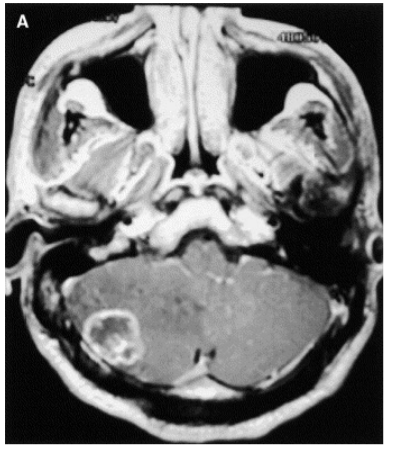

Considere um paciente masculino 55 anos com historia de hemiparesia direita há 2 semanas, sem nenhum fato significante de antecedente.

De acordo com a imagem acima, dentre os diagnósticos abaixo descritos, qual o mais provável?